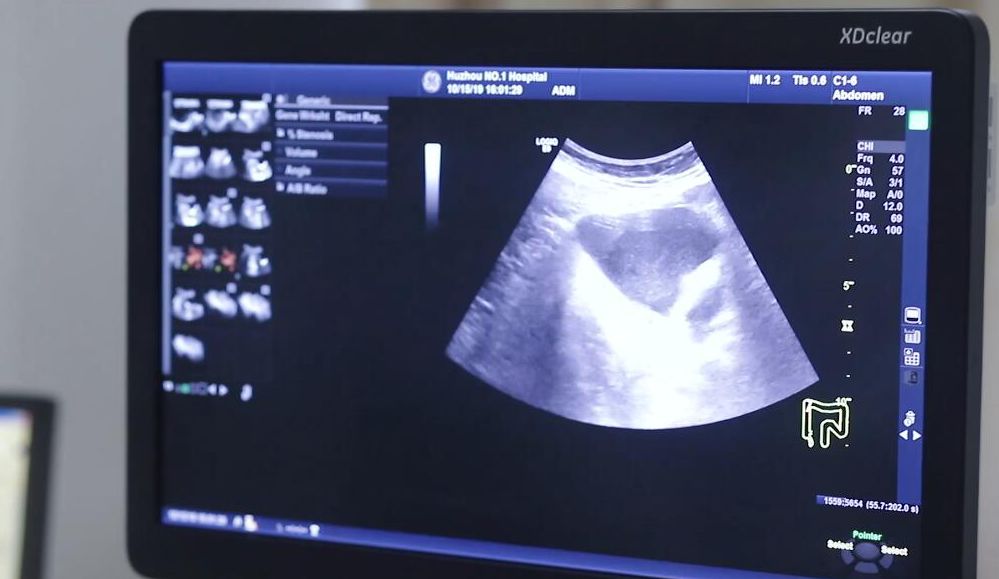

湖州市医学会超声医学专业委员会主任委员湖州市第一人民医院超声医学科主任中国民族卫生协会超声医学分会副会长中国医药教育协会超声医学专委会常委兼胃肠超声学组副主任委员中国超声医学工程学会介入超声专委会委员中国医师协会超声医师分会腹部专委会委员 自1988年开始从事胃肠超声技术的研究,经过30余年的不懈努力,总结出一套系统的、规范的、全面的胃肠超声技术的检查操作方法,在胃肠道肿瘤、消化性溃疡、阑尾疾病、胃肠道急腹症及大网膜肠系膜疾病等超声检查及介入诊疗方面具有较高的造诣;于2004年撰写出版了专著《临床胃肠疾病超声诊断学》,填补了国内在胃肠超声领域的学术空白。一间黑屋,表情严肃,拿着一个探头,对着一台仪器,在病人身上涂抹着一些粘乎乎的,不知道是什么的东西,这应该就是大部分人对于超声医生的第一印象。但其实,超声医生的工作远没有我们想象的那么简单,今天的《医学会主委风采录》就带大家走近湖州市医学会超声医学专业委员会主任委员陆文明。

遇到不能确定的病例,陆文明一定会第一时间和临床医生沟通,甚至去到手术室,实时比对标本和医学影像,力求将所有疑问全部消除。正是这样的探知精神,使得陆文明的眼光愈加毒辣,别人看不出的问题,到他这一眼就能看出,久而久之,他的同事们就给他起了个打趣的外号,叫陆半仙。